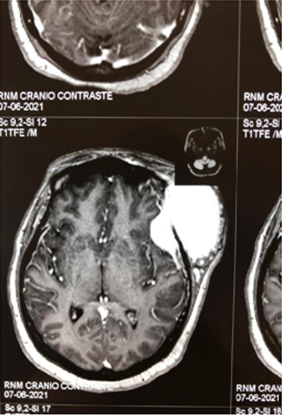

Figure 2A Contrast-enhanced magnetic resonance imaging showing a tumor in the extraaxial region of left frontal involvement.

Figure 2B Contrast-enhanced magnetic resonance image showing a tumor in the extraaxial region of left frontal involvement.